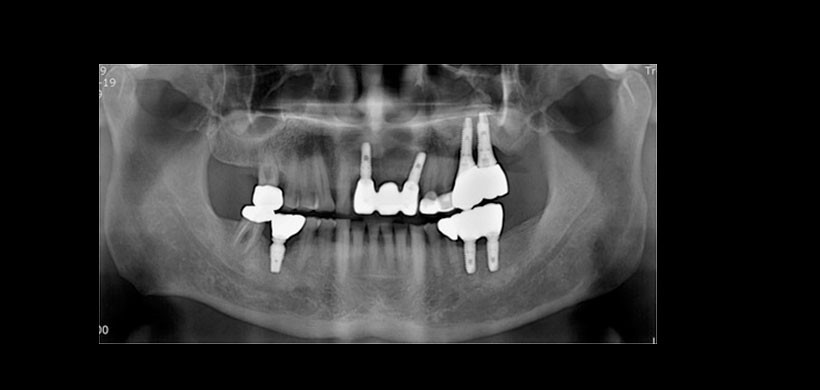

Figura 1: a) Vista panorámica preoperatoria y b) Vista de la tomografía computarizada cone beam (CBCT)